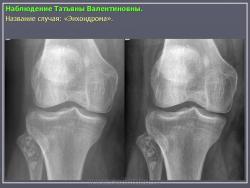

Энхондрома (син.: хондрома, центральная хондрома) — доброкачественная хрящевая опухоль, расположенная в костномозговом канале (интрамедуллярно). Встречается в 10 % случаев от общего числа доброкачественных опухолей костей. Считается, что она возникает из эктопически расположенных островков хряща, отщепившегося от пластинки роста на ранних этапах онтогенеза. В ряде случаев опухоль остается бессимптомной и обнаруживается случайно при рентгенологическом исследовании. В других случаях возникают боль и припухлость. Обычно болезненными становятся все энхондромы фаланг. Наиболее частая локализация: фаланги, главным образом, пальцев кистей, проксимальный конец плечевой кости, проксимальный или дистальный концы бедренной кости. При рентгенологическом исследовании в энхондроме определяются просветления с участками минерализации. Тень кости становится более широкой, кортикальный слой сохраняет целостность, но истончается. В редких случаях энхондрома имеет вид эксцентрически растущего экзофитного новообразования. Макроскопически опухоль представляет собой голубовато-белую полупрозрачную хрящевую ткань, в которую вкраплены желтоватые участки обызвествления. Опухоль состоит из отдельных хрящевых узелков, диаметр которых варьирует в пределах 1 см.

Рентгенологическая картина хондромы представляет четко очерченный опухолевый узел. Очаги минерализации в хондромах выглядят достаточно характерно и представлены очаговыми, глыбчатыми или кольцевидными , арочными отложениями извести. Полного разрушения кортикального слоя трубчатой кости с выходом опухолевых масс в мягкие ткани не наблюдается.